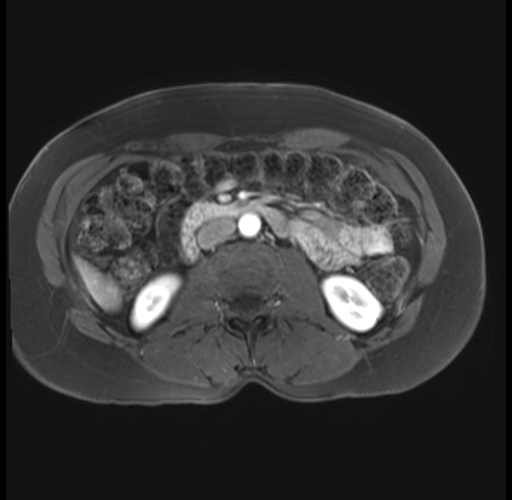

Imaging Analysis

Look through the patient's CT scan to identify any areas of concern for the necessary procedure.

Based on your CT findings, which issue(s) are present and would give reason for "planned slowing down moment(s)" in this case?